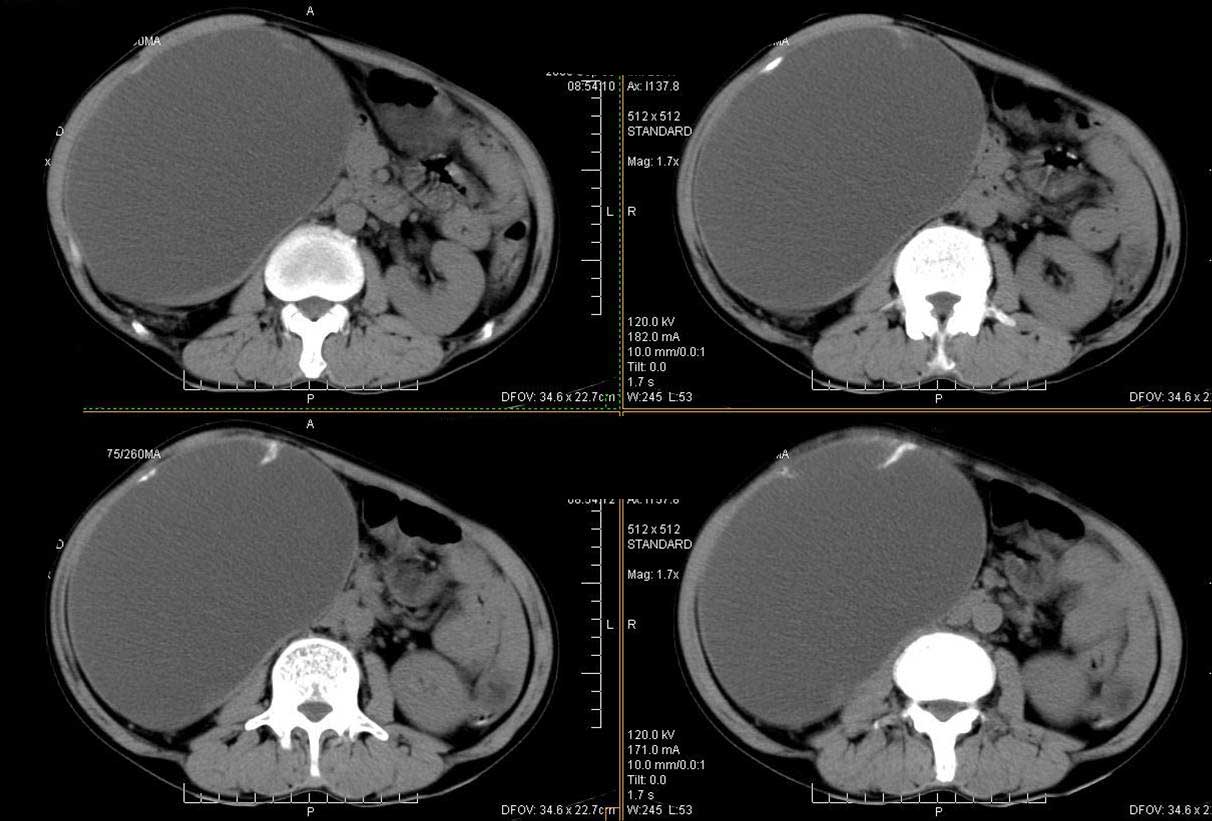

ct值测量

平扫

动脉期

门脉期